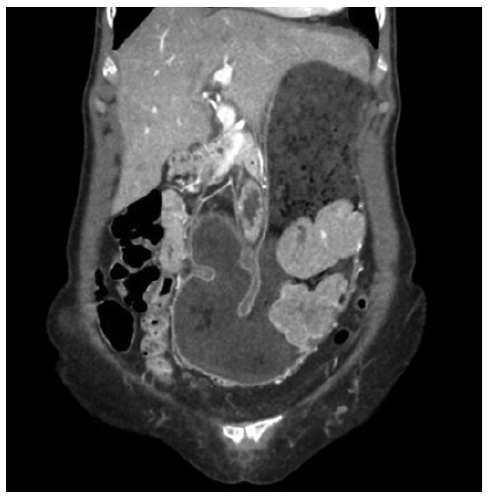

We present a 71-year-old female with no relevant past medical history. The patient was started on a proton pump inhibitor for dyspepsia, with complete symptomatic improvement. One year later, there was symptom recurrence with weight loss. Upper endoscopy revealed a 10 cm gastric subepithelial lesion, with central erosion (Fig. 1). Pathology evaluation was negative for malignancy. Computed tomography showed an extensive gastric wall lesion, with no adenopathies (Fig. 2). Endoscopic ultrasound (EUS) evaluation revealed an 8 cm subepithelial polycyclic hypoechoic lesion, with transition zone suggestive of the third/fourth layer origin (Fig. 3a). Quantitative elastography evaluation showed strain histogram 68 (Fig. 3b). The fine needle biopsy using a 22-G Franseen needle revealed clonal proliferation of plasma cells, positive for CD45/CD138 and negative for CD3/CD20/CD56 (Fig. 4). There was no anemia, hypercalcemia, or kidney impairment, and no abnormalities were found on bone marrow biopsy and myelogram apart from mildly increased plasma cell proliferation (5-10% of total cells). The positron emission tomography/computed tomography scan showed increased gastric uptake, with a maximum standardized uptake value of 3.3. Treatment consisted of surgical resection and the patient had an uneventful postoperative course. The surgical specimen confirmed the diagnosis.